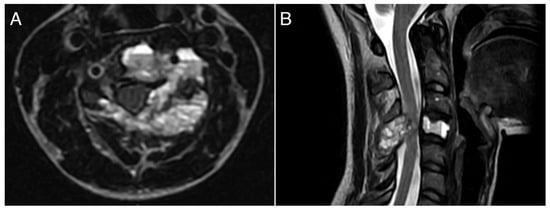

A 26-year-old female with a massively lytic lesion in C4 showed consistent ossification after seven months of treatment (Figure 2 and Figure 3). She chose to discontinue denosumab after 20 administrations due to being asymptomatic and being at her fertile age. However, ten months after stopping the medication, she experienced severe neck and upper left pain, leading her to seek urgent medical attention at the emergency department of our clinic. CT and MRI showed a local recurrence of the ABC in C4 (Figure 4 and Figure 5). She then received a “re-challenge” treatment with denosumab according to the above-mentioned protocol, and the treatment is still ongoing. At the last follow-up, 20 months after being on denosumab with a monthly schedule, the patient was asymptomatic, and the last CT showed good ossification of C4 (43 months follow-up from the first treatment).

Figure 3. CT scan performed at seven months of treatment with denosumab, showing significant ossification of the lesion. (A): axial view; (B): sagittal view.